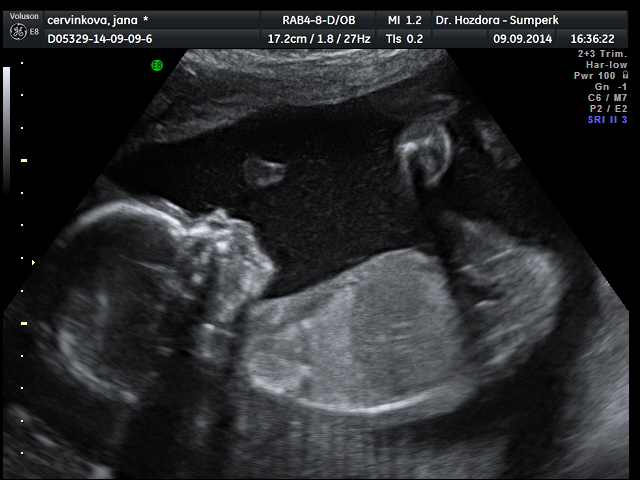

Děvčata,tak mám po velkém ultrazvuku a v lednu se nám narodí zdravá holčička jménem Marie Jana

Jani, úplně mě zalechtalo u srdíčka, ty fotky jsou nádherné. Já bych do 4D taky šla, je to sice dost peněz, ale je to na celý život